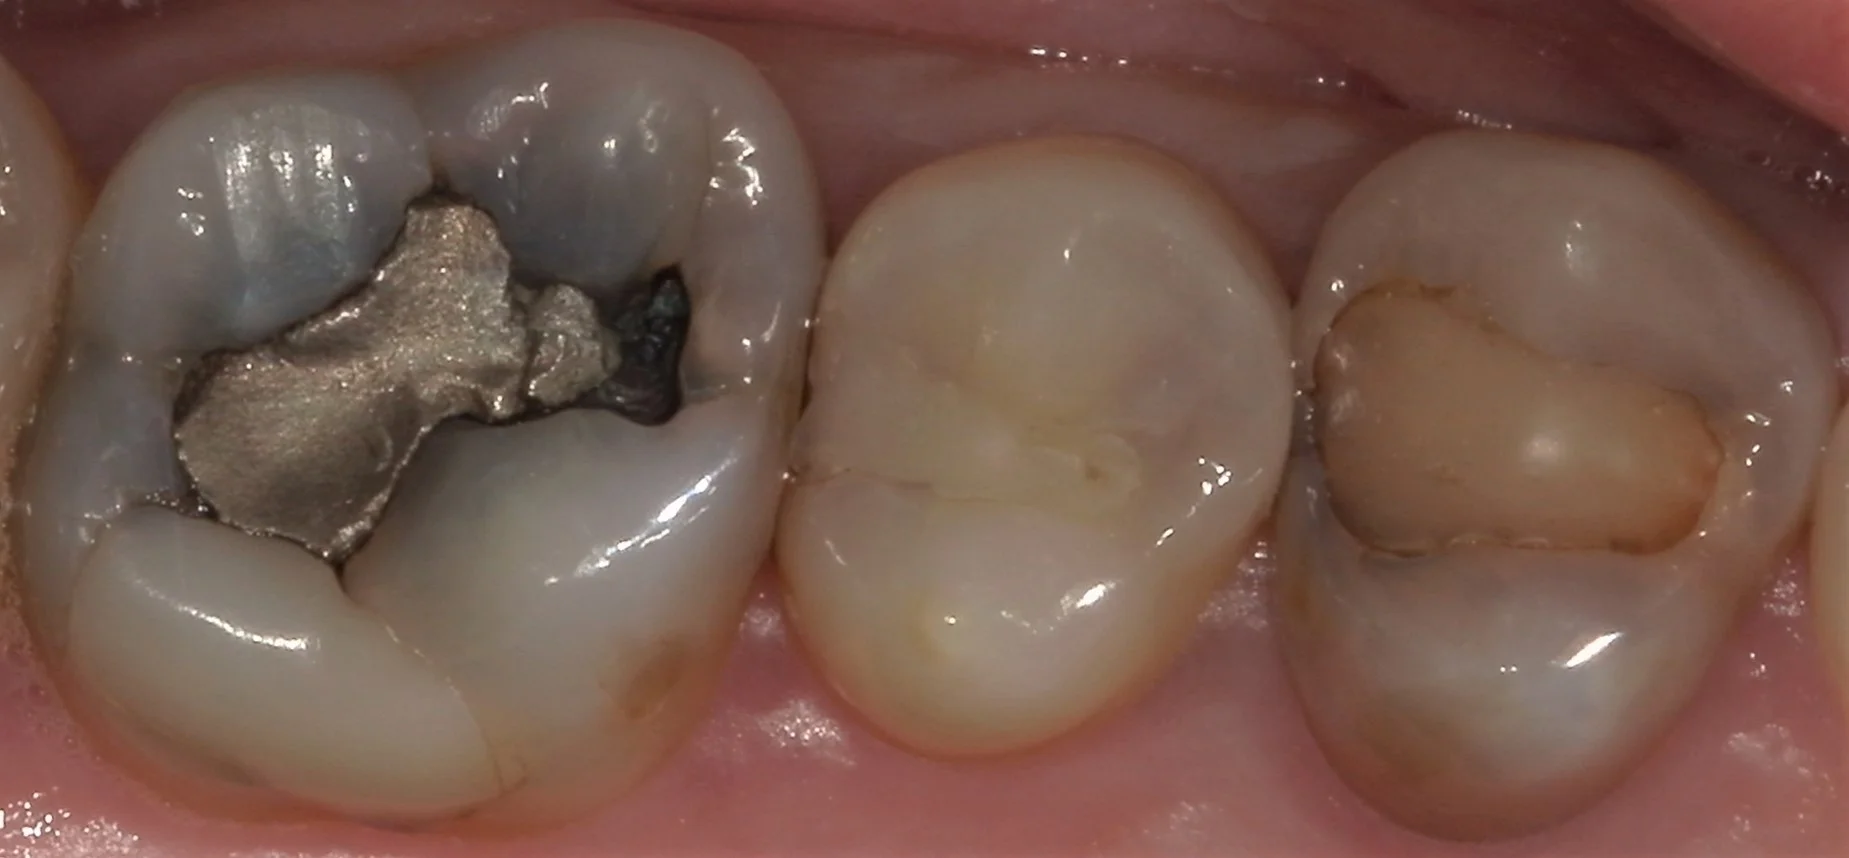

では術前の写真からです。

こちらの写真の中で実は最も神経に近かったのはレントゲン診査上、真ん中の歯でした。

そのため、本日は真ん中の歯のみ治療し、後日前後の歯を治療するという治療計画に変更いたしました。